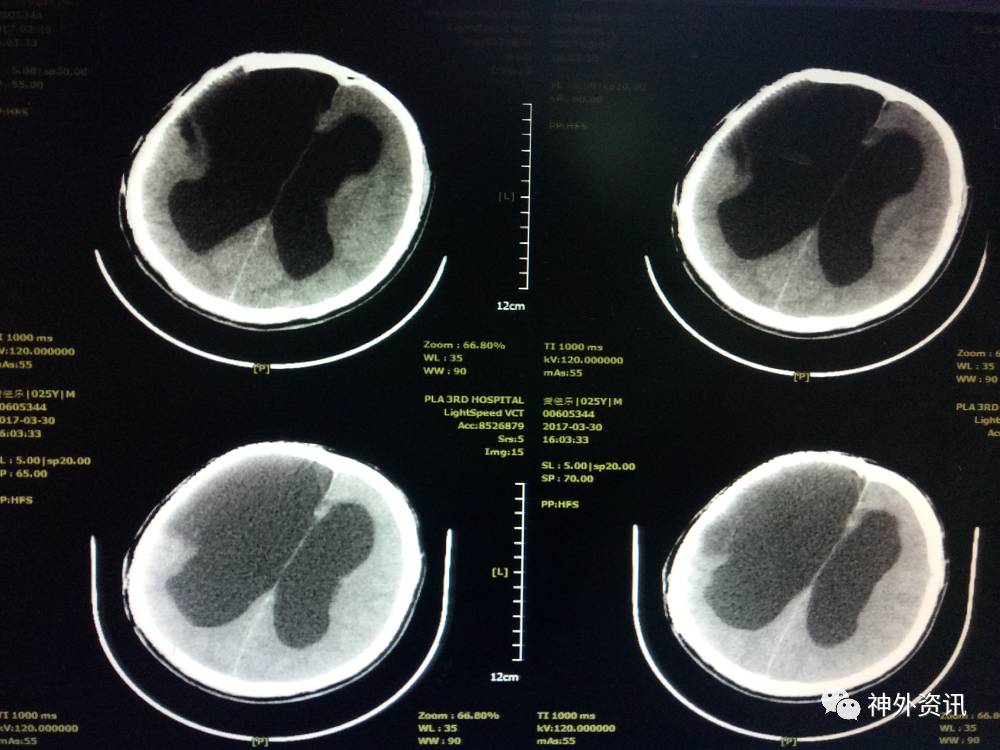

后患者逐渐康复,未再行脑室腹腔分流术,耐受良好,于2017年3月复查头颅CT未见脑室明显扩大,意识清楚,言语清晰,对答切题,扶物下可自主行走,生活大部分基本自理。

2017-03-30头颅CT示:

2016年3月,患者恢复良好,轻度辅助下可行走。